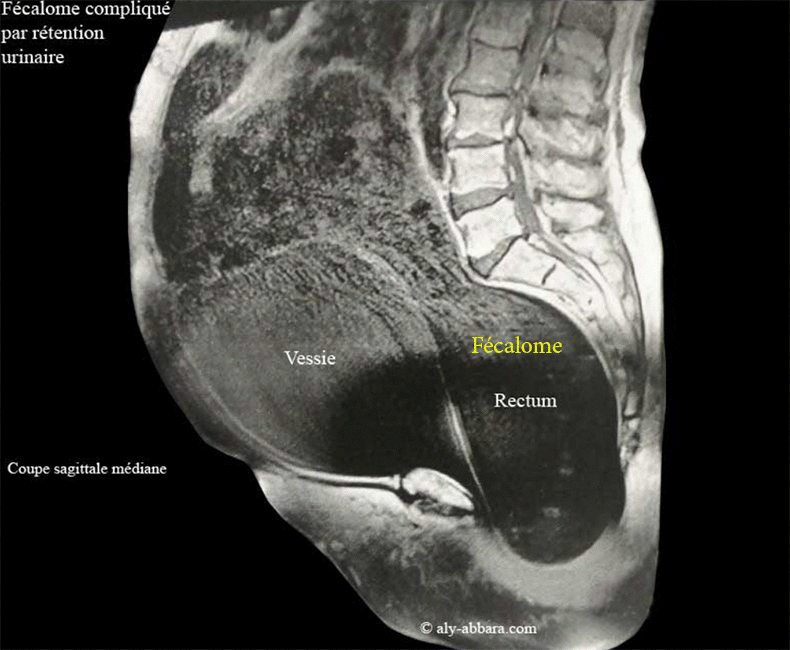

Fécalome provoquant une dysurie (rétention urinaire) chez patiente très âgée

Volumineux fécalome se manifestant par rétention fécale (constipation prolongée) et une rétention urinaire avec miction par regorgement

Il s'agit d'une patiente âgée de 92 ans, ayant dans ses antécédents une hystérectomie totale avec annexectomie bilatérale à l'âge de 48 ans pour utérus myomateux ; elle se présente aux urgences pour une constipation chronique et prolongée, douleurs abdomino-pelviennes et l'impossibilité d'effectuer une miction urinaire normale (miction par regorgement) ; l'ensemble de ces symptômes dure depuis plusieurs semaines. L'examen clinique (le toucher rectal et toucher vaginal) met en évidance la présence de ce volumineux fécalome ; puis un volumineux globe vésicale nécessitant la réalisation de cette IRM quelques jours auparavant.